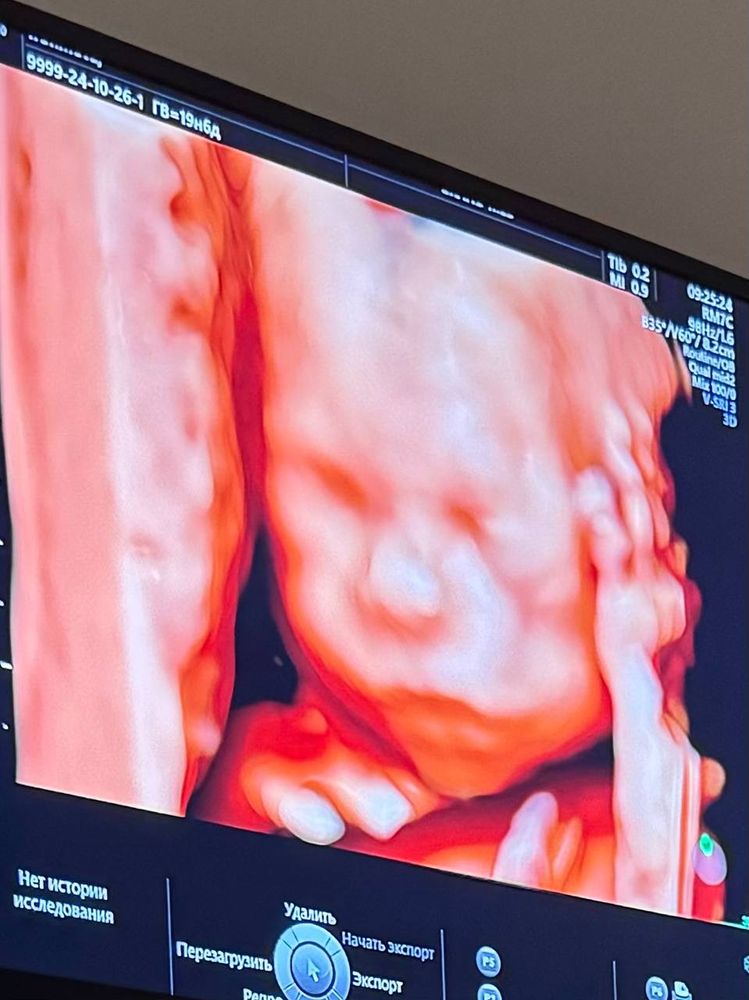

Скрининг 19 Недель Фото

Скрининг 19 Недель Фото 120 фото

13 14 Недель Беременности Фото